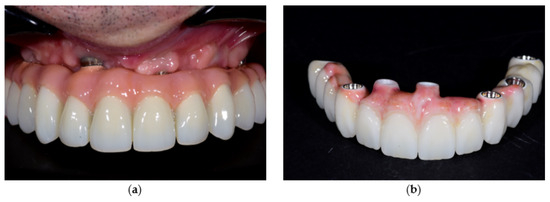

Case Report

Restorations with Zirconia Fixed Bridges over One-Piece Zirconia Implants and PEEK Telescopic Crowns: A Mini-Review and Case Report

by Haseeb H. Al Dary, Layla A. Abu-Naba’a, Hussein H. Helal and Mahmoud M. Hasasna

Ceramic dental implants, particularly one-piece zirconia, offer a biocompatible and aesthetic alternative to titanium, with high strength and improved oral hygiene. By eliminating the implant–abutment micro-gap, they reduce bacterial accumulation because of their low plaque affinity and enhance stability. However, challenges remain, including [...] Read more.

Ceramic dental implants, particularly one-piece zirconia, offer a biocompatible and aesthetic alternative to titanium, with high strength and improved oral hygiene. By eliminating the implant–abutment micro-gap, they reduce bacterial accumulation because of their low plaque affinity and enhance stability. However, challenges remain, including alignment precision, limited retrievability, and sensitivity to mechanical stress. Misalignment can affect occlusal and functional outcomes, and zirconia’s rigidity complicates crown removal and modification. This case report explores the use of PEEK (polyether ether ketone) primary telescopic crowns to overcome these limitations, improving force distribution, enabling minor adjustments, and enhancing prosthetic retrievability in full-mouth zirconia restorations. A 62-year-old male patient seeking a fixed solution to replace removable dentures received 16 one-piece zirconia implants (eight per jaw). PEEK telescopic crowns were used over implant abutment copings, finalized with aesthetic zirconia bridges. The report details surgical and prosthetic procedures, along with a brief literature review on zirconia implants and PEEK applications. PEEK integration in telescopic prosthetic designs marks a notable advancement in prosthodontics. Its shock-absorbing, biocompatible, and stress-modulating properties make it valuable for implant-supported and hybrid restorations. As digital workflows advance, PEEK-based telescopic restorations may increasingly replace traditional metal-based solutions, improving long-term clinical outcomes. Further clinical research on a larger sample is needed. Full article